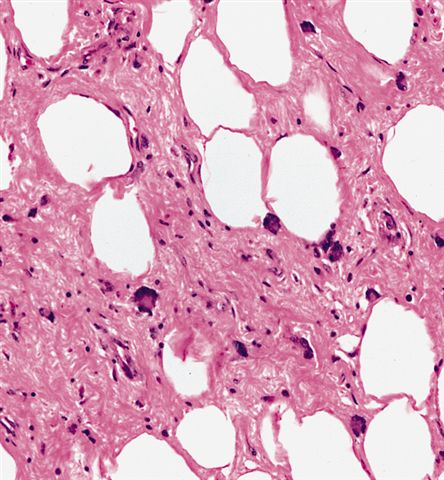

Microscopic (histologic) images

Contributed by Michael Clay, M.D., Melanie Bourgeau, M.D. and AFIP

Morphologic variability:

- Lipoma-like subtype

- Most common subtype

- Scattered atypical cells may be diffuse or exceedingly rare

- Frequently contains lipoblasts

- Grossly, can be indistinguishable from lipoma

- Depends on subtype, generally composed of mature fat with variably sized adipocytes and bands of fibrotic stroma containing spindle cells with enlarged, hyperchromatic nuclei

- Can be markedly atypical

- Cellularity is low and mitotic figures are uncommon

- Atypical cells are more commonly found in fibrous septa and in a perivascular distribution